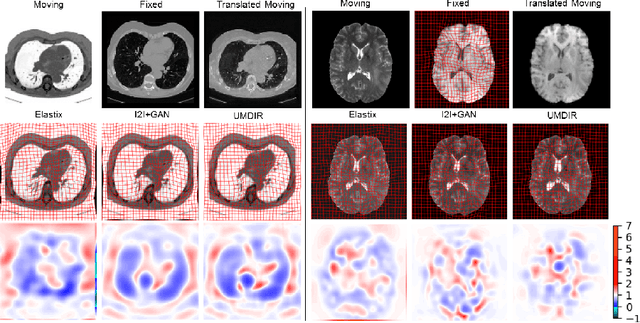

Abstract:We propose a fully unsupervised multi-modal deformable image registration method (UMDIR), which does not require any ground truth deformation fields or any aligned multi-modal image pairs during training. Multi-modal registration is a key problem in many medical image analysis applications. It is very challenging due to complicated and unknown relationships between different modalities. In this paper, we propose an unsupervised learning approach to reduce the multi-modal registration problem to a mono-modal one through image disentangling. In particular, we decompose images of both modalities into a common latent shape space and separate latent appearance spaces via an unsupervised multi-modal image-to-image translation approach. The proposed registration approach is then built on the factorized latent shape code, with the assumption that the intrinsic shape deformation existing in original image domain is preserved in this latent space. Specifically, two metrics have been proposed for training the proposed network: a latent similarity metric defined in the common shape space and a learningbased image similarity metric based on an adversarial loss. We examined different variations of our proposed approach and compared them with conventional state-of-the-art multi-modal registration methods. Results show that our proposed methods achieve competitive performance against other methods at substantially reduced computation time.